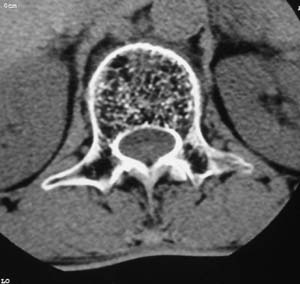

以下是引用余辉在2008-4-27 17:12:00的发言:[br]骨质疏松伴病理性压缩性骨折,椎骨骨松质密度减低,椎体骨小梁稀疏且普遍呈火柴头样改变,椎体无膨胀,无软组织肿块

以下是引用mzh123在2008-4-27 19:33:00的发言:[br]除压缩骨折表现外 还有许莫氏结节改变

以下是引用随光逐影在2008-4-27 21:29:00的发言:[br]除压缩性骨折外,还有许莫氏结节及骨质疏松表现。